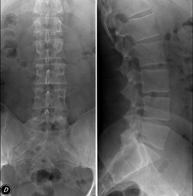

- Columna

- RX Columna cervical

Tècnica que usa els raigs X a través de la qual s'obtenen imatges de la columna cervical per al seu estudi. Indicacions: traumatisme, dolor cervical. - RX Columna dorsal

Tècnica que usa els raigs X a través de la qual s'obtenen imatges de la columna dorsal per al seu estudi. Indicacions: traumatisme, mal d'esquena. - RX Columna lumbar

Tècnica que usa els raigs X a través de la qual s'obtenen imatges de la columna lumbar per al seu estudi. Indicacions: ciàtica, traumatisme, dolor lumbar. - RX Sacre-còccix

Tècnica que usa els raigs X a través de la qual s'obtenen imatges del sacre i del còccix per al seu estudi. Indicacions: traumatisme, dolor sacre o coccigi. - Telerradiologia columna

Tècnica que usa els raigs X a través de la qual s'obtenen imatges de tota la columna vertebral per al seu estudi, amb la valoració especialment de la presència d'escoliosi i dismetries pèlviques.